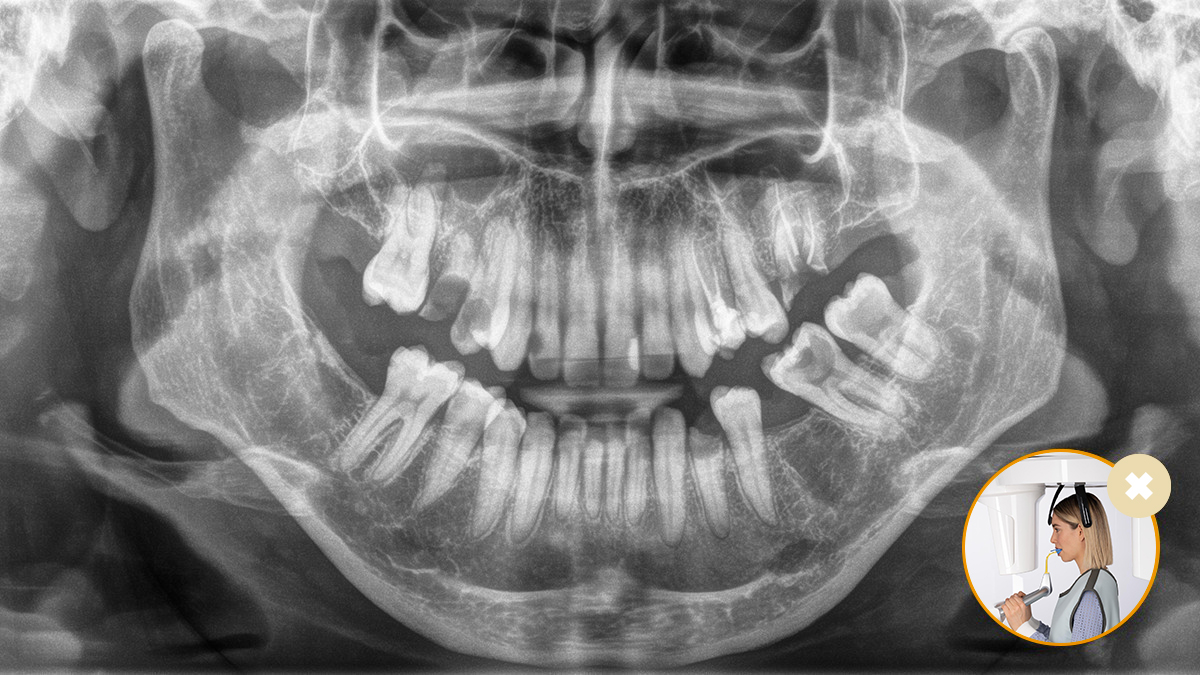

Un correcto posicionamiento del paciente contribuye a mejorar su experiencia, ya que con imágenes de alta calidad se consigue un diagnóstico más preciso.

Este concepto de 10 puntos facilita la colocación del paciente y la adquisición de imágenes radiológicas. Se fundamenta sobre todo en dos aspectos: unas imágenes de alta calidad y la mayor comodidad para el paciente y el asistente.

El manejo del mordedor oclusal no puede ser más sencillo. Gracias a los símbolos y colores que aparecen en la pantalla del equipo de radiología, los médicos cuentan con toda la información necesaria para ajustar el dispositivo lo mejor posible. Las flechas iluminadas señalizan en qué dirección hay que mover la unidad para que la cabeza tenga la mejor inclinación. El dispositivo se detiene automáticamente cuando llega a la posición correcta.